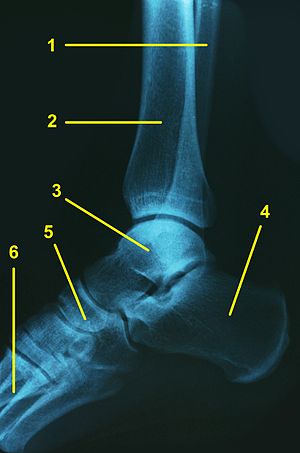

Sprunggelenk

Legende:

1 – Wadenbein (Fibula)

2 – Schienbein (Tibia)

3 – Sprungbein (Talus)

4 – Fersenbein (Calcaneus)

5 – Kahnbein (Os naviculare)

6 – Mittelfußknochen (Os metatarsi)